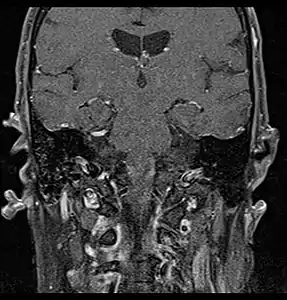

Coronal MRI showing right parotid adenoid cystic carcinoma with perineural spread of tumor: The tumor originates in the right parotid gland and spreads along the trigeminal nerve via the auricuotemporal branch extending intracranially through the foramen ovale at the skull base towards Meckel's cave.

Coronal MRI showing right parotid adenoid cystic carcinoma with perineural spread of tumor along the facial nerve extending to the stylomastoid foramen